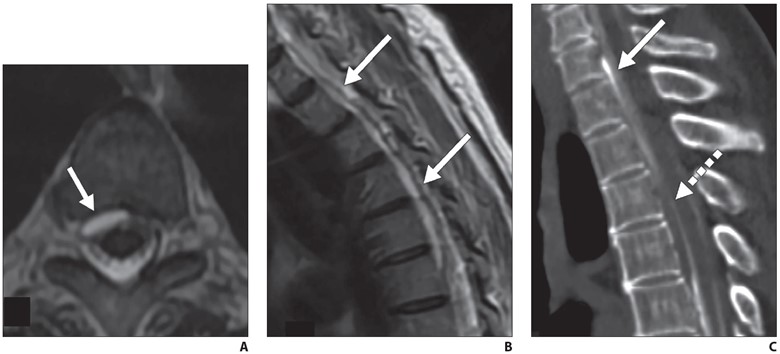

In contrast to CVF localization, pressure augmentation and inspiration maneuvers are not necessary when locating fast leaks from a violation of the ventral or lateral dura. After injection of contrast material into the subarachnoid space, the patient’s hips are elevated and rapid whole spine imaging is performed. Images should be scrutinized for where contrast material first moves from the subarachnoid to the epidural space, filling the epidural fluid collection or lateral epidural space (Fig. 6).

Fig. 6—72-year-old woman with orthostatic headaches.

A and B, Axial (A) and sagittal (B) T2-weighted MR images through thoracic spine show ventral epidural fluid collection extends from T1 to T6 (arrows).

C, Sagittal prone early-phase dynamic myelogram shows filling of ventral epidural fluid collection at C7-T1 level with dense contrast material (solid arrow), while more inferior component of collection (dashed arrow) has not yet filled, suggesting that dural defect is at C7-T1 level.